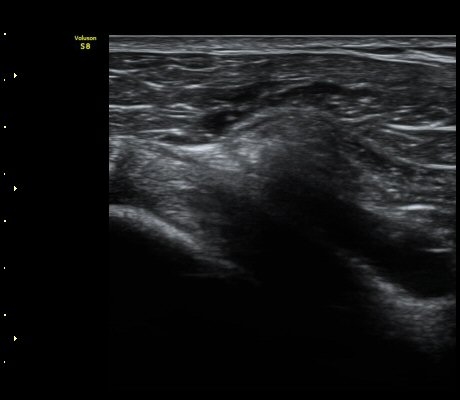

±Ø»ó°Ç Á¾´Ü¸é°Ë»ç»ó ±Ø»ó°Ç ³»Ãø ºÎÂøºÎ¿¡¼­ °Ç¿¬°á¼º ¼Ò½ÇÀÌ °üÂûµÈ´Ù(±×¸² 7, 8).

±Ø»ó°Ç Á¾´Ü¸é°Ë»ç»ó ±Ø»ó°Ç ¼Ò½Ç¿¡ ÀÇÇÑ È¸Àü±Ù°³ °á¼ÕÀÌ °üÂûµÈ´Ù(±×¸² 9, 10).